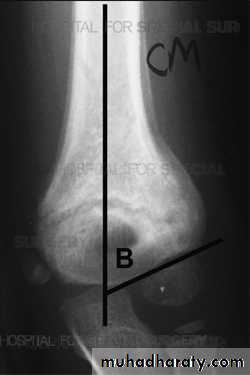

Supracondylar humeral fracture in children is one of the most common fractures seen in the pediatric orthopedic clinic setting worldwide. It's a fracture that occurs at the supracondylar area or the metaphysis of the distal humerus & accounts for 65.4% of upper extremity fractures in children .There are two types of supracondylar fractures in children according to direction of displacement of distal fragment i.e. extension type (97%) and flexion (3%).X-ray of elbow joint (lat. View)

The fracture can however be difficult to identify and often a joint effusion is used to increase one's suspicion of the presence of a fracture. Upon examination the doctor will evaluate the arm for signs of damage to the nerves and blood vessels; they will look for swelling and deformity. This will allow the doctor to determine a likely diagnosis. Damage to the elbow is a common injury in children; injuries to blood supply of the arm may necessitate early surgical intervention. The radiographic study of the injured limb should include an anteroposterior (AP) and a lateral view.(AP) –view ( Lat.) –view